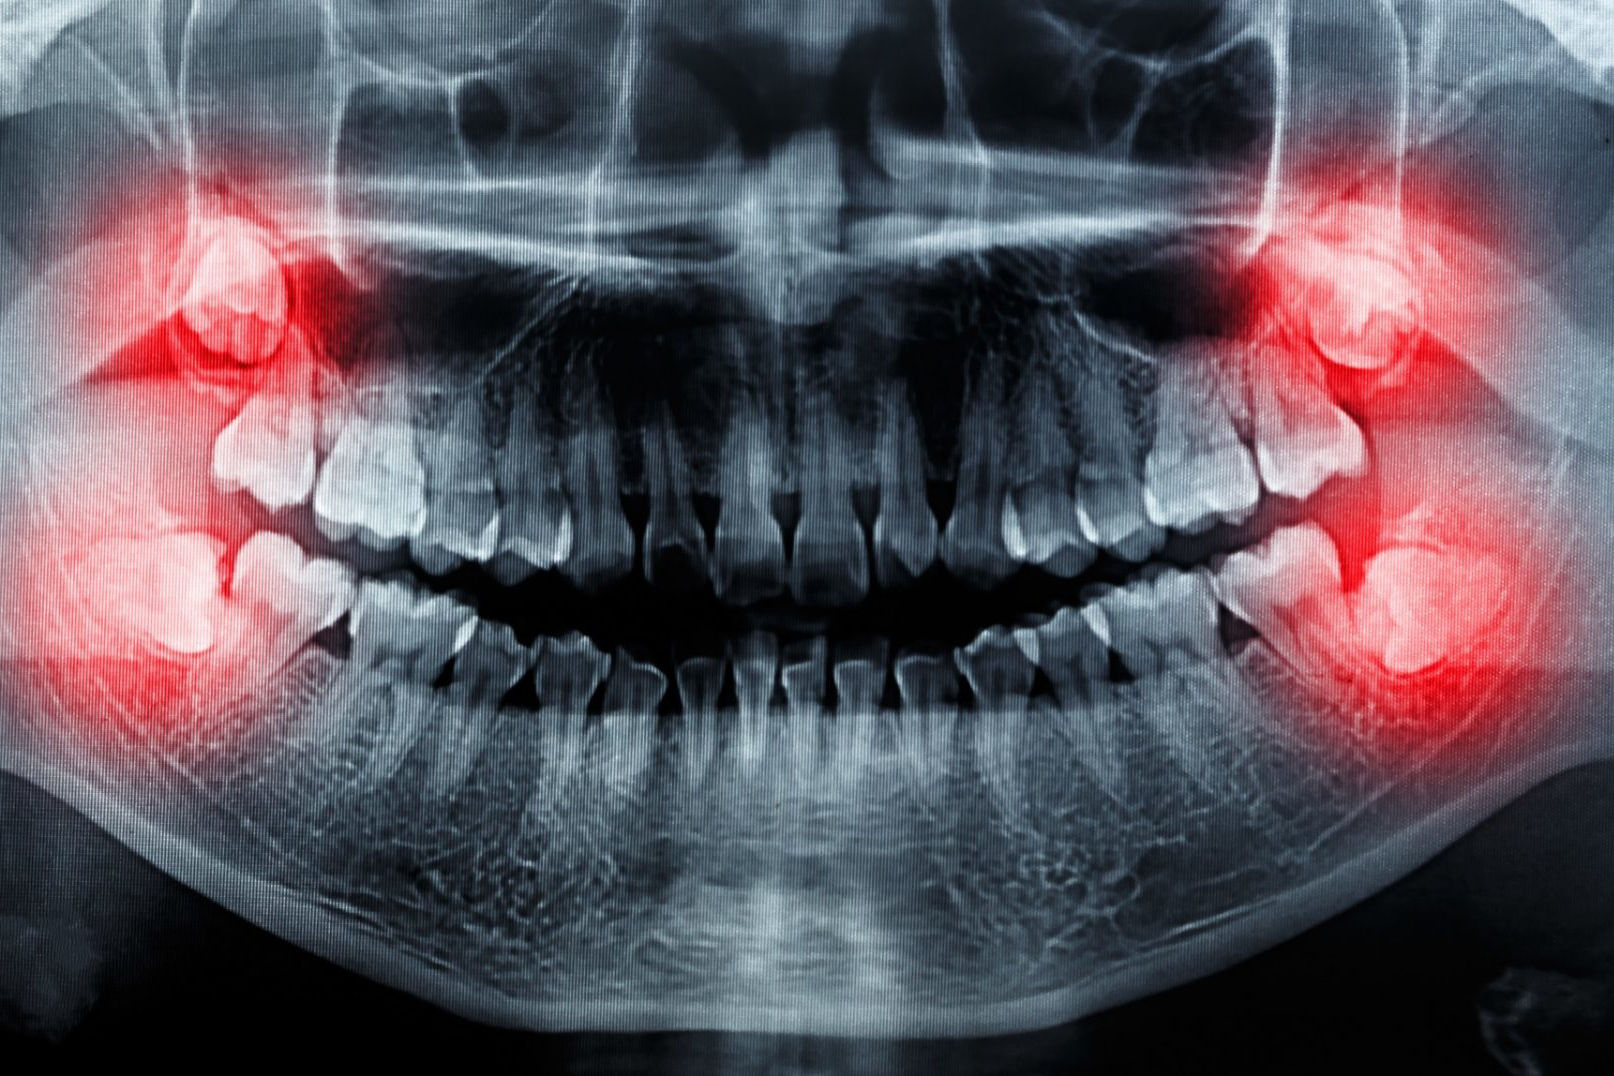

Chirurgische extraktionen – entfernung von Weisheitszähnen

Weisheitszähne sind in der Regel stark verankert, haben 3-4 Wurzeln und erfordern eine chirurgische Behandlung, um entfernt werden zu können. Weiterhin erleben wir oft, dass Weisheitszähne einwachsen, da sie auf verschiedene Weise im Kiefer stirnrunzeln können und ihre Position meist von der normalen abweicht. Dies lässt sich dadurch erklären, dass das Gesichtsskelett, insbesondere der Kiefer, im Laufe der Jahrtausende kleiner geworden ist und somit weniger Platz für die gleiche Anzahl von Zähnen zur Verfügung steht. Es kommt immer häufiger vor, dass sich die Weisheitszähne gar nicht bilden, so dass der glückliche Patient keine Probleme mit ihnen hat, da die Weisheitszähne durchkommen und den nötigen Platz haben.

Welche symptome können bei Weisheitszähnen auftreten und warum?

Wenn ein Weisheitszahn nicht vollständig anwachsen kann und auf halber Strecke stehen bleibt, kann er sich entzünden. Auch die Reinigung dieser Zähne kann kompliziert sein, was zusätzlich für Entzündungen sorgen kann, auch unter dem Gaumen. Das kann Schmerzen, Karies und schlechten Mundgeruch verursachen.

Auch können sich Weisheitszähne in schlechter Lage negativ auf andere Zähne auswirken, zum Beispiel könnten sich die Zähne auf den Druck der Weisheitszähne nach innen bewegen, was zu Verzerrungen oder Stockung der anderen Zähne führen kann. In diesen Fällen muss dann oft eine Zahnsange für die Korrektur angewandt werden.